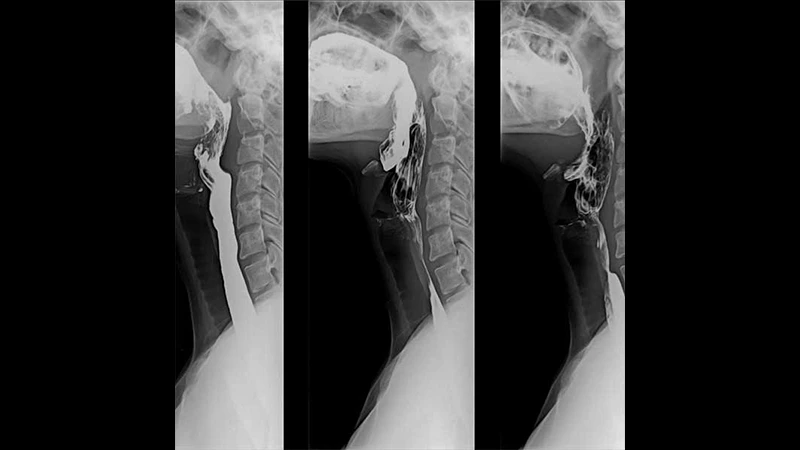

- Barium: A dense, chalky liquid that is swallowed or administered as an enema to visualize the gastrointestinal (GI) tract.

- Gastrointestinal Studies: In a barium swallow or upper GI series, a radiologist watches the contrast move through the esophagus, stomach, and small intestine to diagnose swallowing problems, ulcers, or blockages.